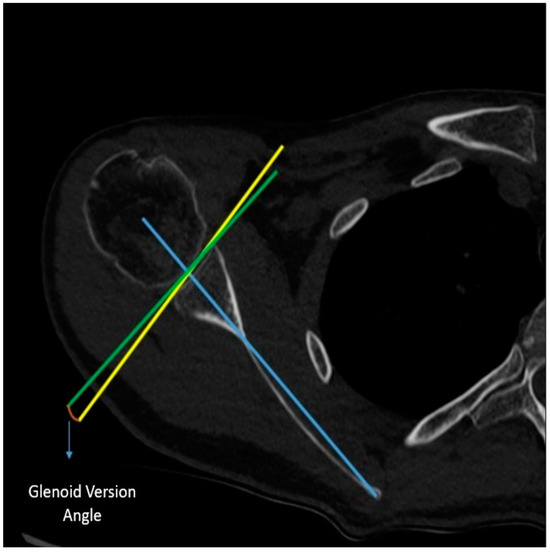

Measurement of Alpha Angle: An axial CT image of the glenohumeral joint is captured. The most prominent subcortical points of the anterior and posterior corners of the glenoid are connected. In the axial section, the angle between this line and the body of the screw is referred to as the alpha angle (Figure 1).

Figure 1. Measurement of the alpha angle on postoperative CT.